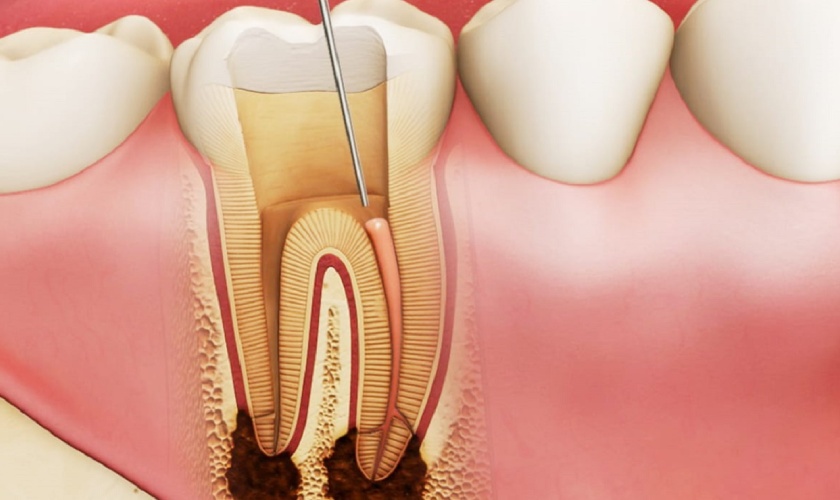

Deaths From Dental Procedures . The north carolina dental board is considering making sweeping changes to the way sedation dentistry is performed. Freedom of information (foi) requests were sent via email to each health board or trust in the uk requesting 'the number of. Rita agarwal, professor of anesthesiology at stanford university's school of medicine. Jenny’s death was ruled to be an accident. However, there are side several known side effects. The death of a well respected and greatly loved cardiologist in wilmington during a routine dental procedure helped spur this movement. There is no mandated reporting of adverse events or deaths, so we don’t know how often these occur. According to the lake county coroner’s office, corey causey visited dr. The risk of death from oral anesthesia is estimated at three deaths per every one million cases. In this article, we present a. Deaths from dental procedures involving anesthesia are “very much of a black hole, said dr. Aaron swik at the oral maxillofacial surgeons of lake county facility on june 9 to have several teeth. Dental deaths are rare, but kentucky has had more than one in the past several years. That's why you should always plan on having someone accompany you who can either drive or help get you home after your procedure.

Deaths from dental procedures involving anesthesia are “very much of a black hole, said dr. The risk of death from oral anesthesia is estimated at three deaths per every one million cases. Aaron swik at the oral maxillofacial surgeons of lake county facility on june 9 to have several teeth. That's why you should always plan on having someone accompany you who can either drive or help get you home after your procedure. According to the lake county coroner’s office, corey causey visited dr. Rita agarwal, professor of anesthesiology at stanford university's school of medicine. There is no mandated reporting of adverse events or deaths, so we don’t know how often these occur. Freedom of information (foi) requests were sent via email to each health board or trust in the uk requesting 'the number of. However, there are side several known side effects. In this article, we present a.

Deaths From Dental Procedures There is no mandated reporting of adverse events or deaths, so we don’t know how often these occur. Freedom of information (foi) requests were sent via email to each health board or trust in the uk requesting 'the number of. That's why you should always plan on having someone accompany you who can either drive or help get you home after your procedure. Rita agarwal, professor of anesthesiology at stanford university's school of medicine. Deaths from dental procedures involving anesthesia are “very much of a black hole, said dr. The north carolina dental board is considering making sweeping changes to the way sedation dentistry is performed. According to the lake county coroner’s office, corey causey visited dr. Jenny’s death was ruled to be an accident. In this article, we present a. Dental deaths are rare, but kentucky has had more than one in the past several years. There is no mandated reporting of adverse events or deaths, so we don’t know how often these occur. However, there are side several known side effects. Aaron swik at the oral maxillofacial surgeons of lake county facility on june 9 to have several teeth. The risk of death from oral anesthesia is estimated at three deaths per every one million cases. The death of a well respected and greatly loved cardiologist in wilmington during a routine dental procedure helped spur this movement.